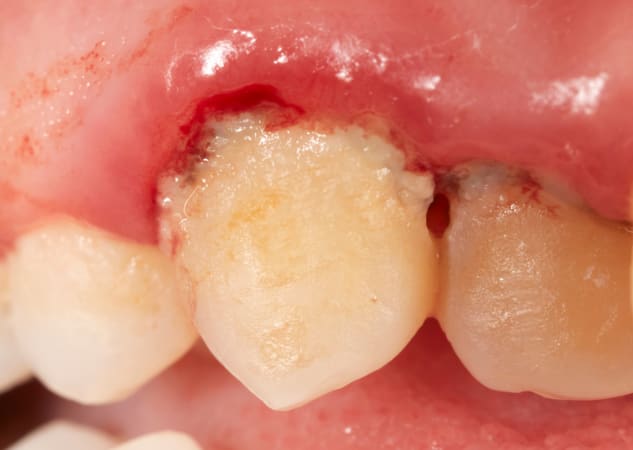

Para que puedas identificarlo visualmente, te ponemos algunas fotos de casos de gingivitis y periodontitis:

Gingivitis